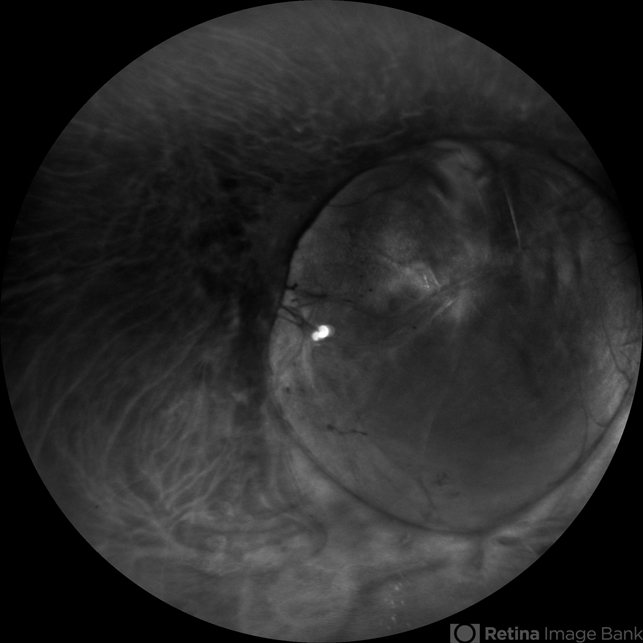

- coloboma, retromode

Scanning laser ophthalmoscope

Mirante, Nidek - Description

- Wide field image of a fundus coloboma taken in retro mode.